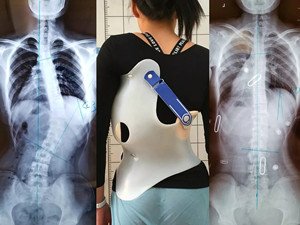

在青少年快速發(fā)育期內(nèi),身體長得越快,脊柱側(cè)彎的進(jìn)展就越快。矯形支具通過長時的反向矯正力將脊柱維持在一個矯正的狀態(tài);然而由于長時間地佩戴支具會導(dǎo)致肌肉萎縮,當(dāng)支具摘除,脊柱側(cè)彎回彈,且患者無法形成成自我矯正力,呼吸功能亦無法得到改善。最好是在穿戴支具的同時,配合體操訓(xùn)練,通過一系列矯正動作以及呼吸訓(xùn)練,平衡肌力,兩者結(jié)合不但可以穩(wěn)定脊柱,且能增加改善機(jī)會。